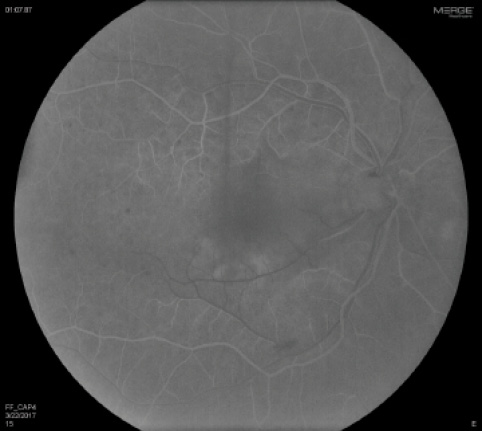

Fluorescein angiography (FA) OD revealed a marked delayed transit time of 40 seconds, poor arterial and venous perfusion, early blocked fluorescence, and hyperfluorescence without late leakage (Figures 3 and 4). SD-OCT imaging revealed drusen without intraretinal or subretinal fluid and nasal hyperreflectivity of the inner retinal layers consistent with acute ischemia (Figure 5). The patient was diagnosed with combined CRAO and CRVO.

Figure 4. FA OD demonstrates delayed transit time and incomplete filling of the retinal arterioles, most notably inferonasally.